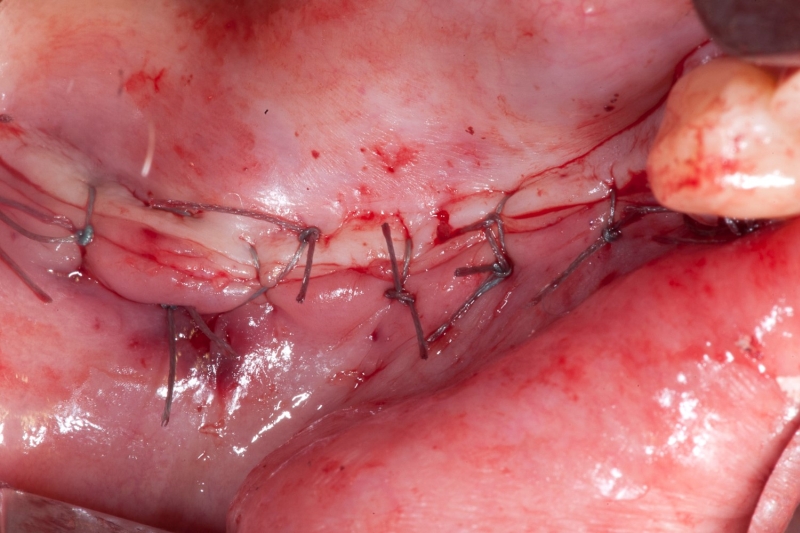

07/18 - Tension-free soft tissue management

Vertical augmentation & sinus lift with maxgraft® bonering - Dr. O. Yüksel and Dr. B. Giesenhagen